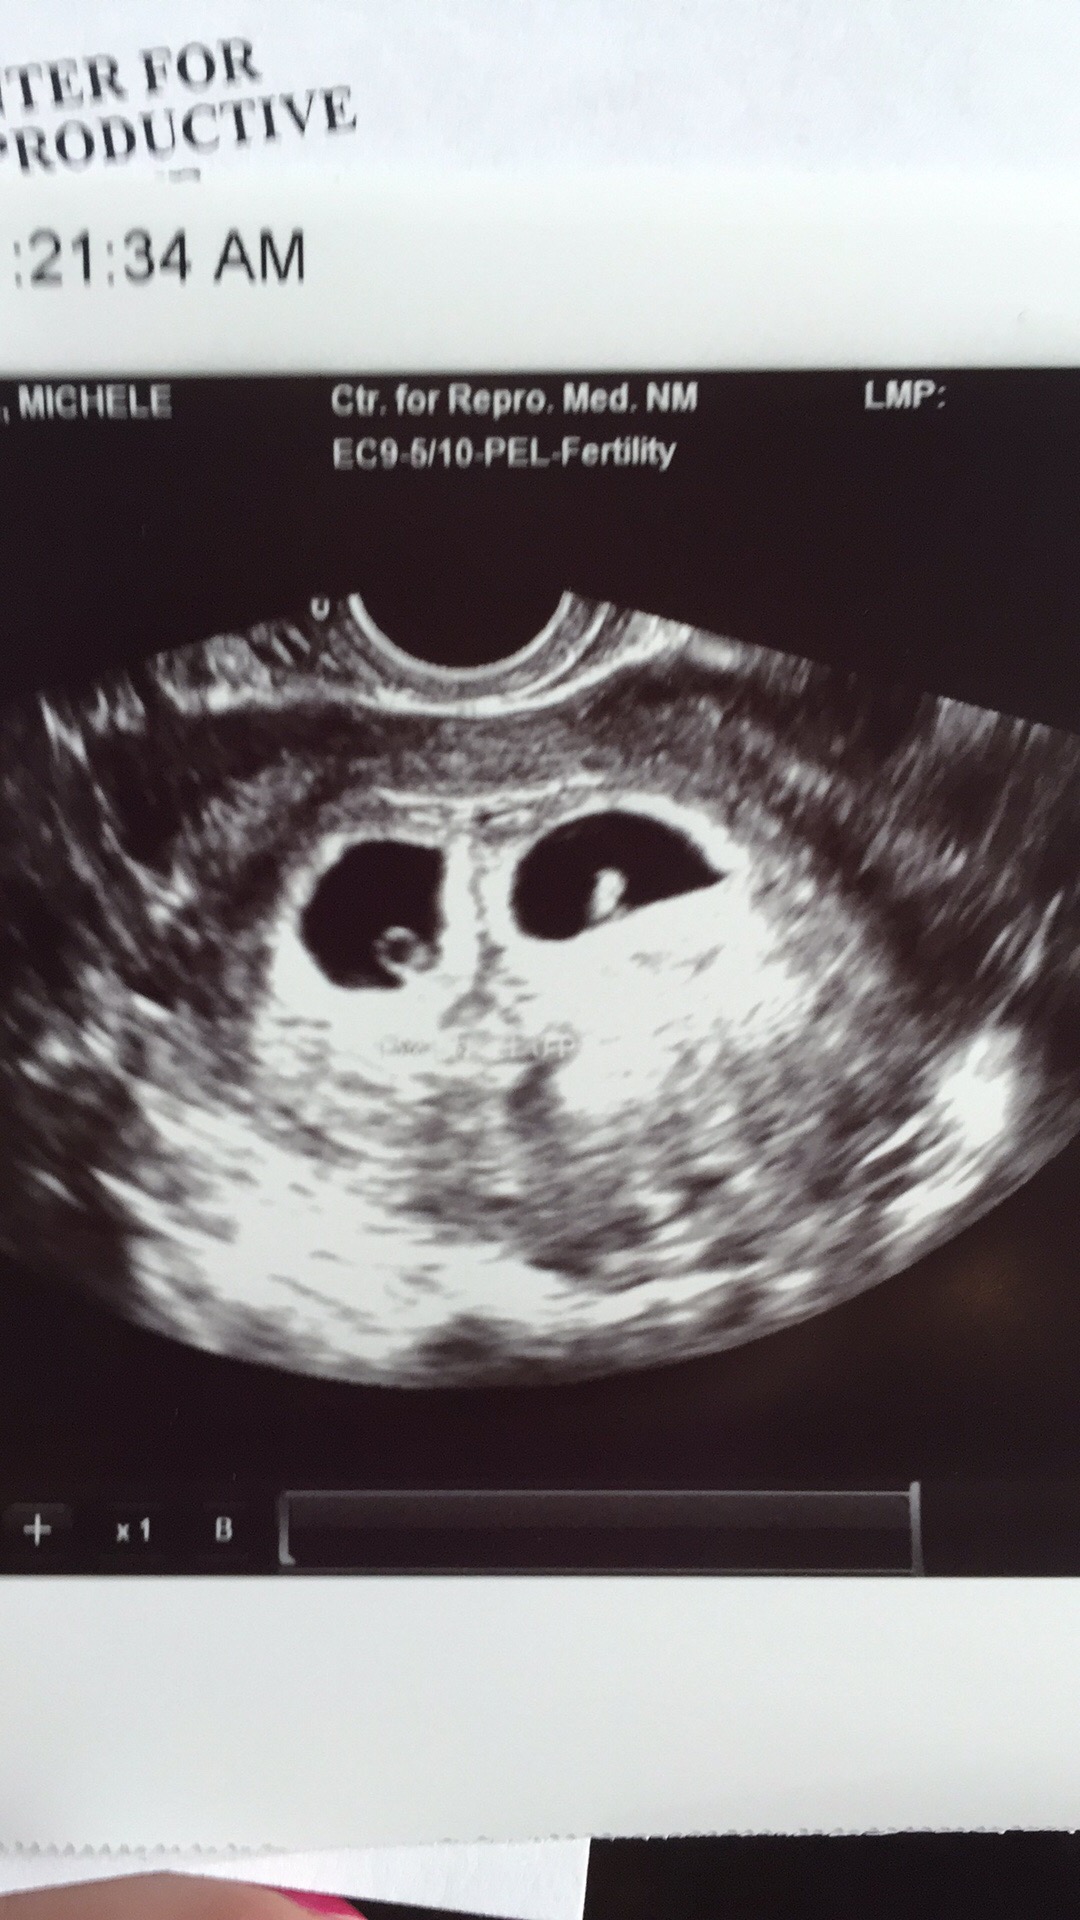

Had my first ultrasound at six weeks holy guacamole

It's TWINS OMG